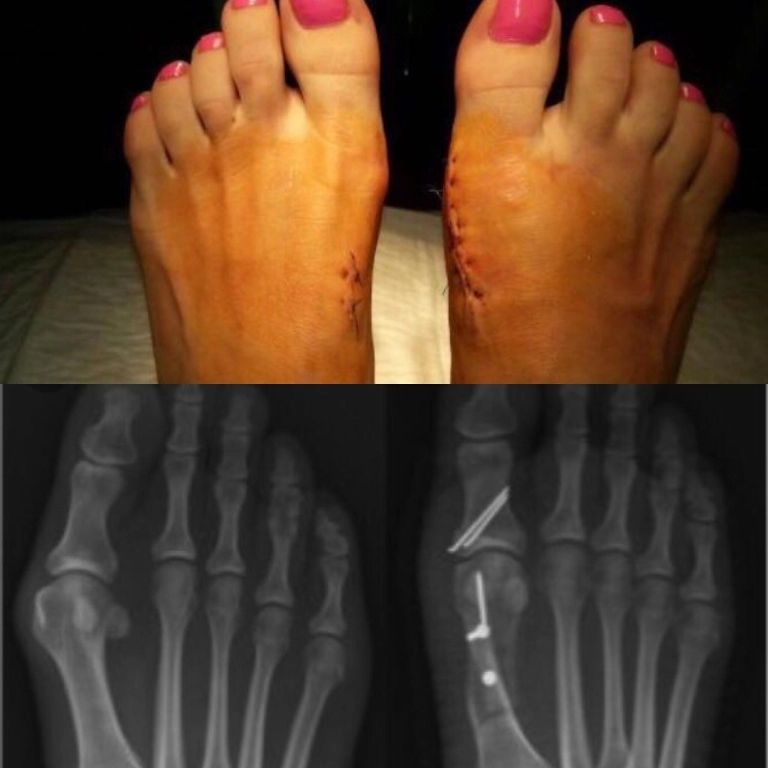

• Также востребованы процедуры по восстановлению связок, остеосинтез костей при переломах разной сложности.